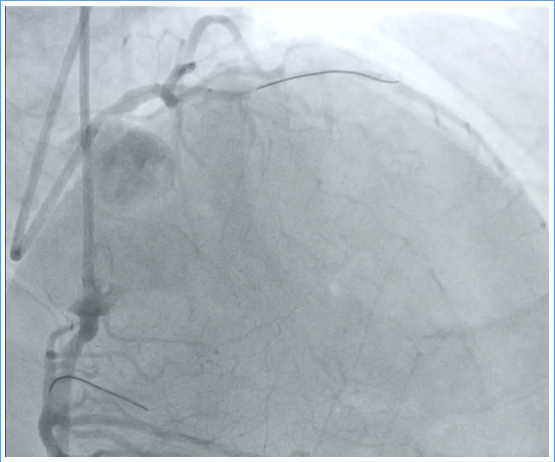

前降支CTO

图片图片